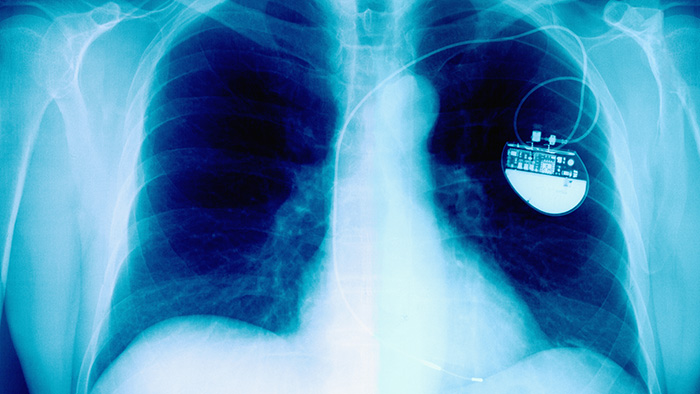

x-ray of chest with pacemaker x-ray of chest with pacemaker

Lead extraction is a minimally invasive procedure to remove pacemaker or implantable cardioverter-defibrillator (ICD) leads from the heart. These leads are insulated wires that extend from your cardiac device through a vein to your heart, delivering electrical signals that help regulate your heartbeat.